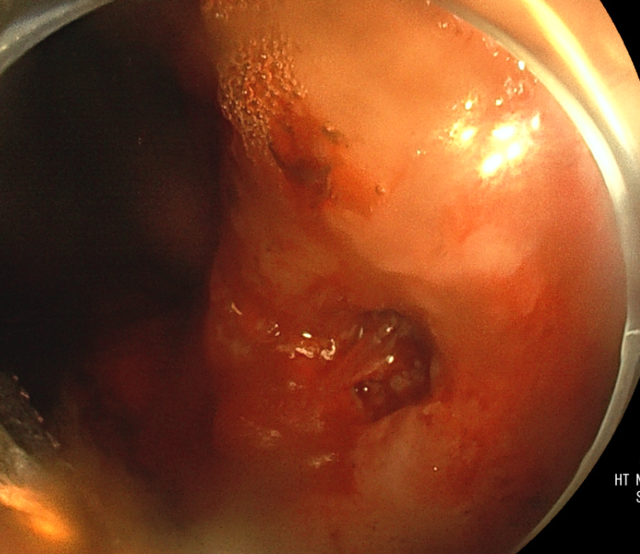

急诊抢救室接诊后立即化验血常规提示血红蛋白61g/L,已临近重度贫血,紧急送往胃镜室,经脾胃肝胆科胃镜检查:胃角见一较深溃疡灶,大小约0.6cm,血管头残留,电凝钳移除血凝块后,见喷射样出血,热凝钳电凝止血后,喷射出血停止,2枚钛夹加固创面,其旁仍见缓慢渗血。

▲ 治疗前